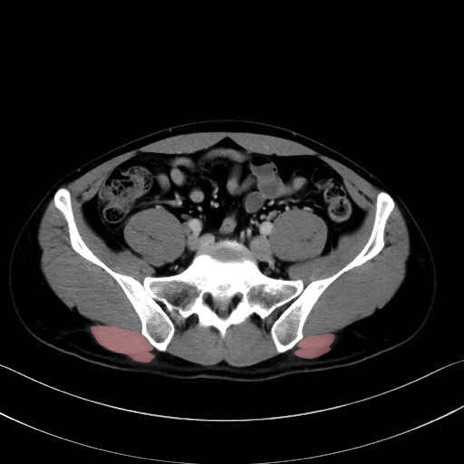

大殿筋 (Gluteus maximus)